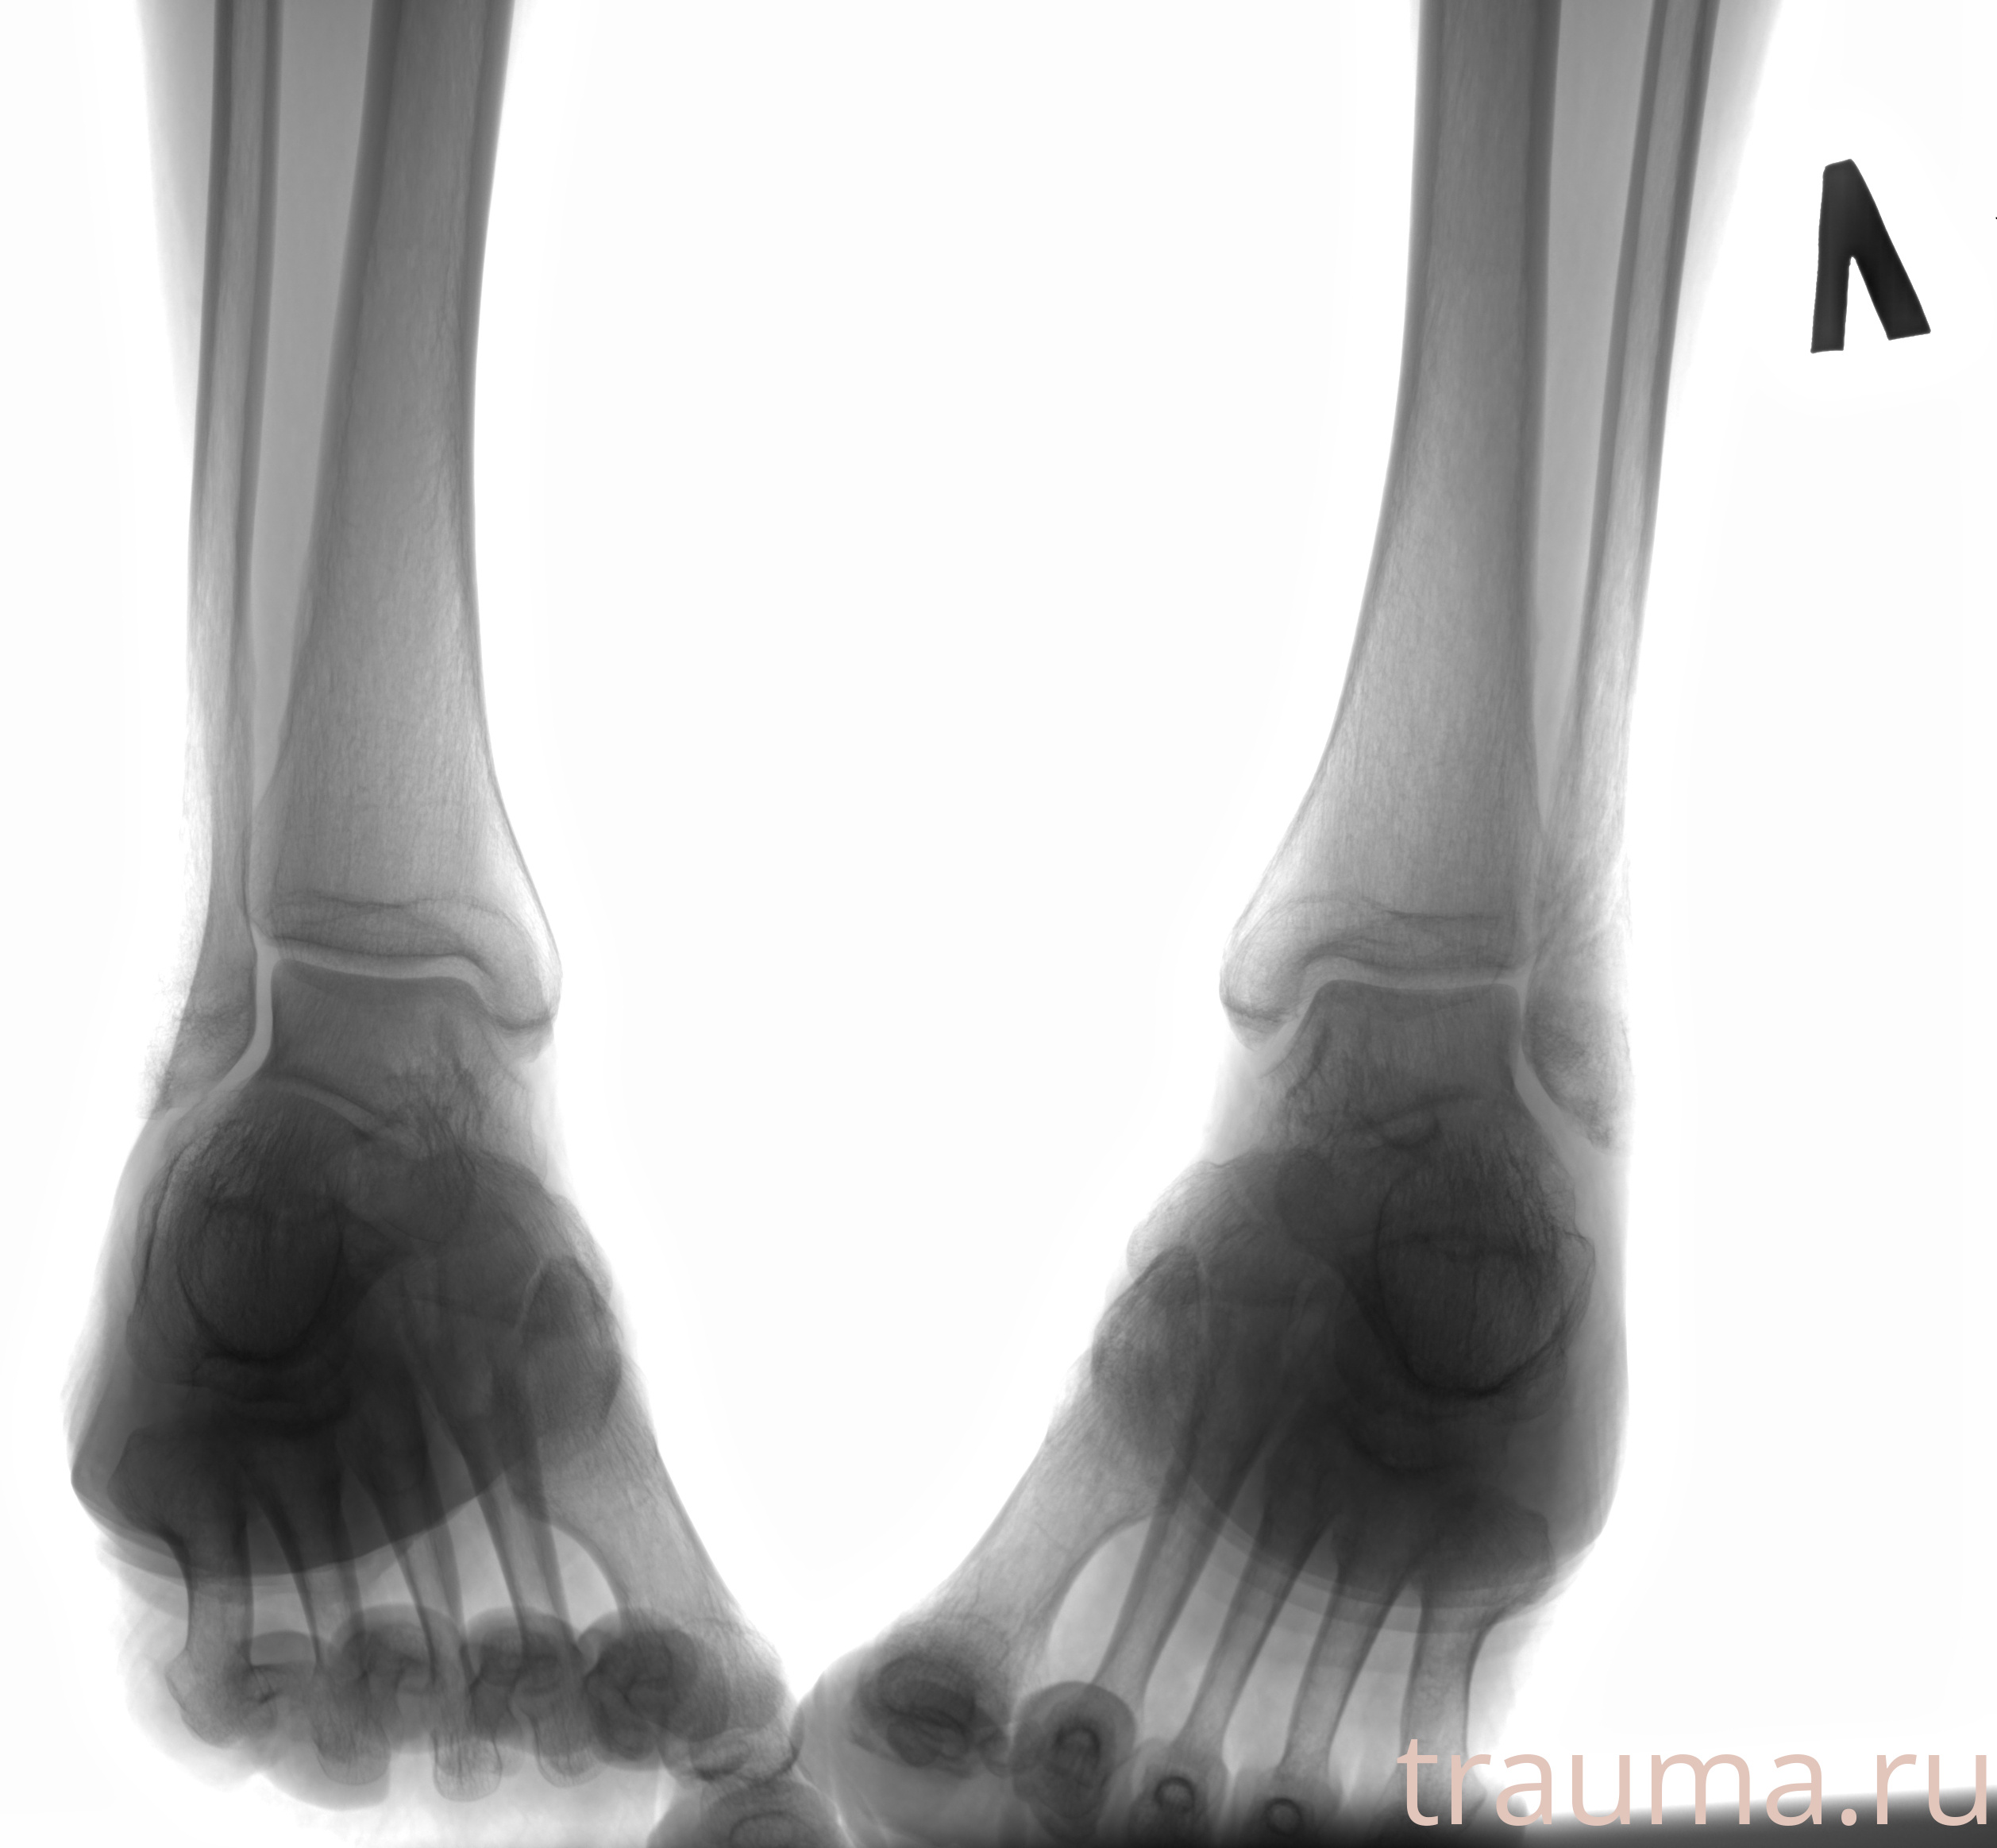

Рентгенограммы

Рентген на дому: по вашему адресу приезжает врач-рентгенолог, травматолог-ортопед с мобильным рентгеновским аппаратом, проводит диагностику травмы или заболевания, делает необходимые рентгенограммы, дает рекомендации по дальнейшему лечению. Получить качественные снимки в домашних условиях возможно благодаря уникальной методике, разработанной МосРентген Центром для института  Склифосовского